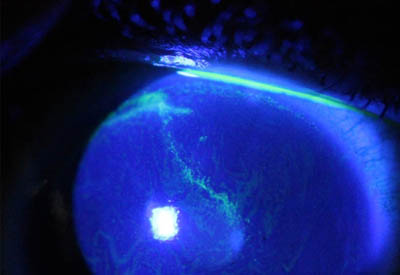

Aspecto Clínico

- Formación de lineas epiteliales elevadas de aspecto granular, que pueden dar imágen de seudodendritas

Perineuritis

No tienen los bulbos terminales de las dendritas del Herpes Simple

Formación de lineas epiteliales elevadas que pueden dar la imagen de Seudodendrítas

Formación de lineas epiteliales elevadas que pueden dar la imagen de Seudodendrítas

Formación de lineas epiteliales elevadas que pueden dar la imagen de Seudodendrítas + Perineuritis

El cuadro clínico inicial progresa, aparecen infiltrados estromales anteriores focales o difusos, edema circunscrito y a veces perineuritis

En su evolución se observará aumento del edema, aparición de un anillo inmunológico (Wessely), agrandamiento y coalescencia de los infiltrados que progresan hacia la formación de un absceso, queratolisis superficial, adelgazamiento y perforación corneal.

Anillo inmunológico de Wessely

- Es la expresión de la interacción de los antígenos extraños con los anticuerpos que se difunden desde los vasos limbares hacia el estroma.

- Representa la formación de un complejo inmune que activa el sistema del complemento.

- El anillo de Wessely contiene principalmente neutrófilos